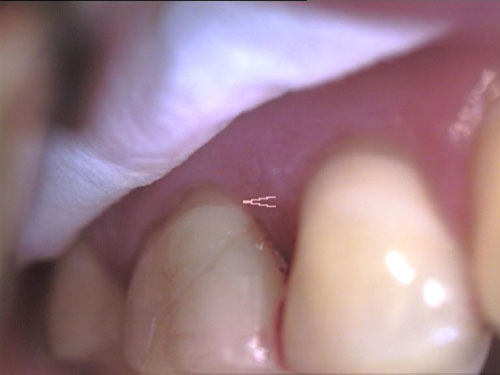

Zahn-Anomalien 1

Zahn-Anomalien 2

Zahn-Anomalien 3

Zahn-Anomalien 4

Zahn-Anomalien 5